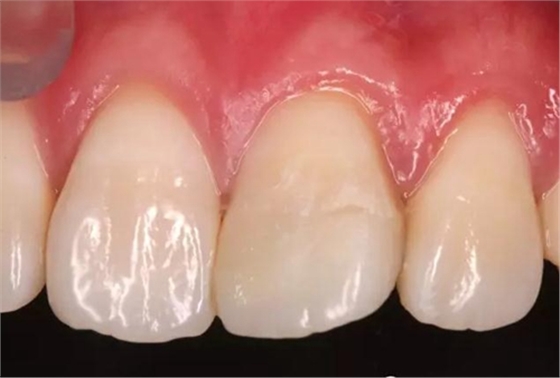

術前口內照

折斷之牙體嚴重脫水,呈白堊色,斷端對位后吻合度較好,僅少許牙體缺損。

口內檢查:21切端牙體色澤恢復,唇側面見水平向粘接界面,殘留少許樹脂水門汀,牙齦腫脹較前消退,叩-,松-。

術后即刻口內照

患者1個半月后復診,口腔衛(wèi)生狀況保持良好,牙齦健康,折斷線不可見。